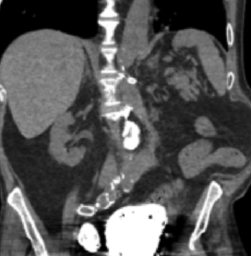

Bensson Samuel, MD, PG Dip, PhD, DBA; Berhanu Geme, MD; Jennifer Axelband, DO; Alden Smith, BA

A 77-year-old male with multiple medical problems presented to the emergency department complaining of right flank pain and decrease in bowel movements.

08/20/2015